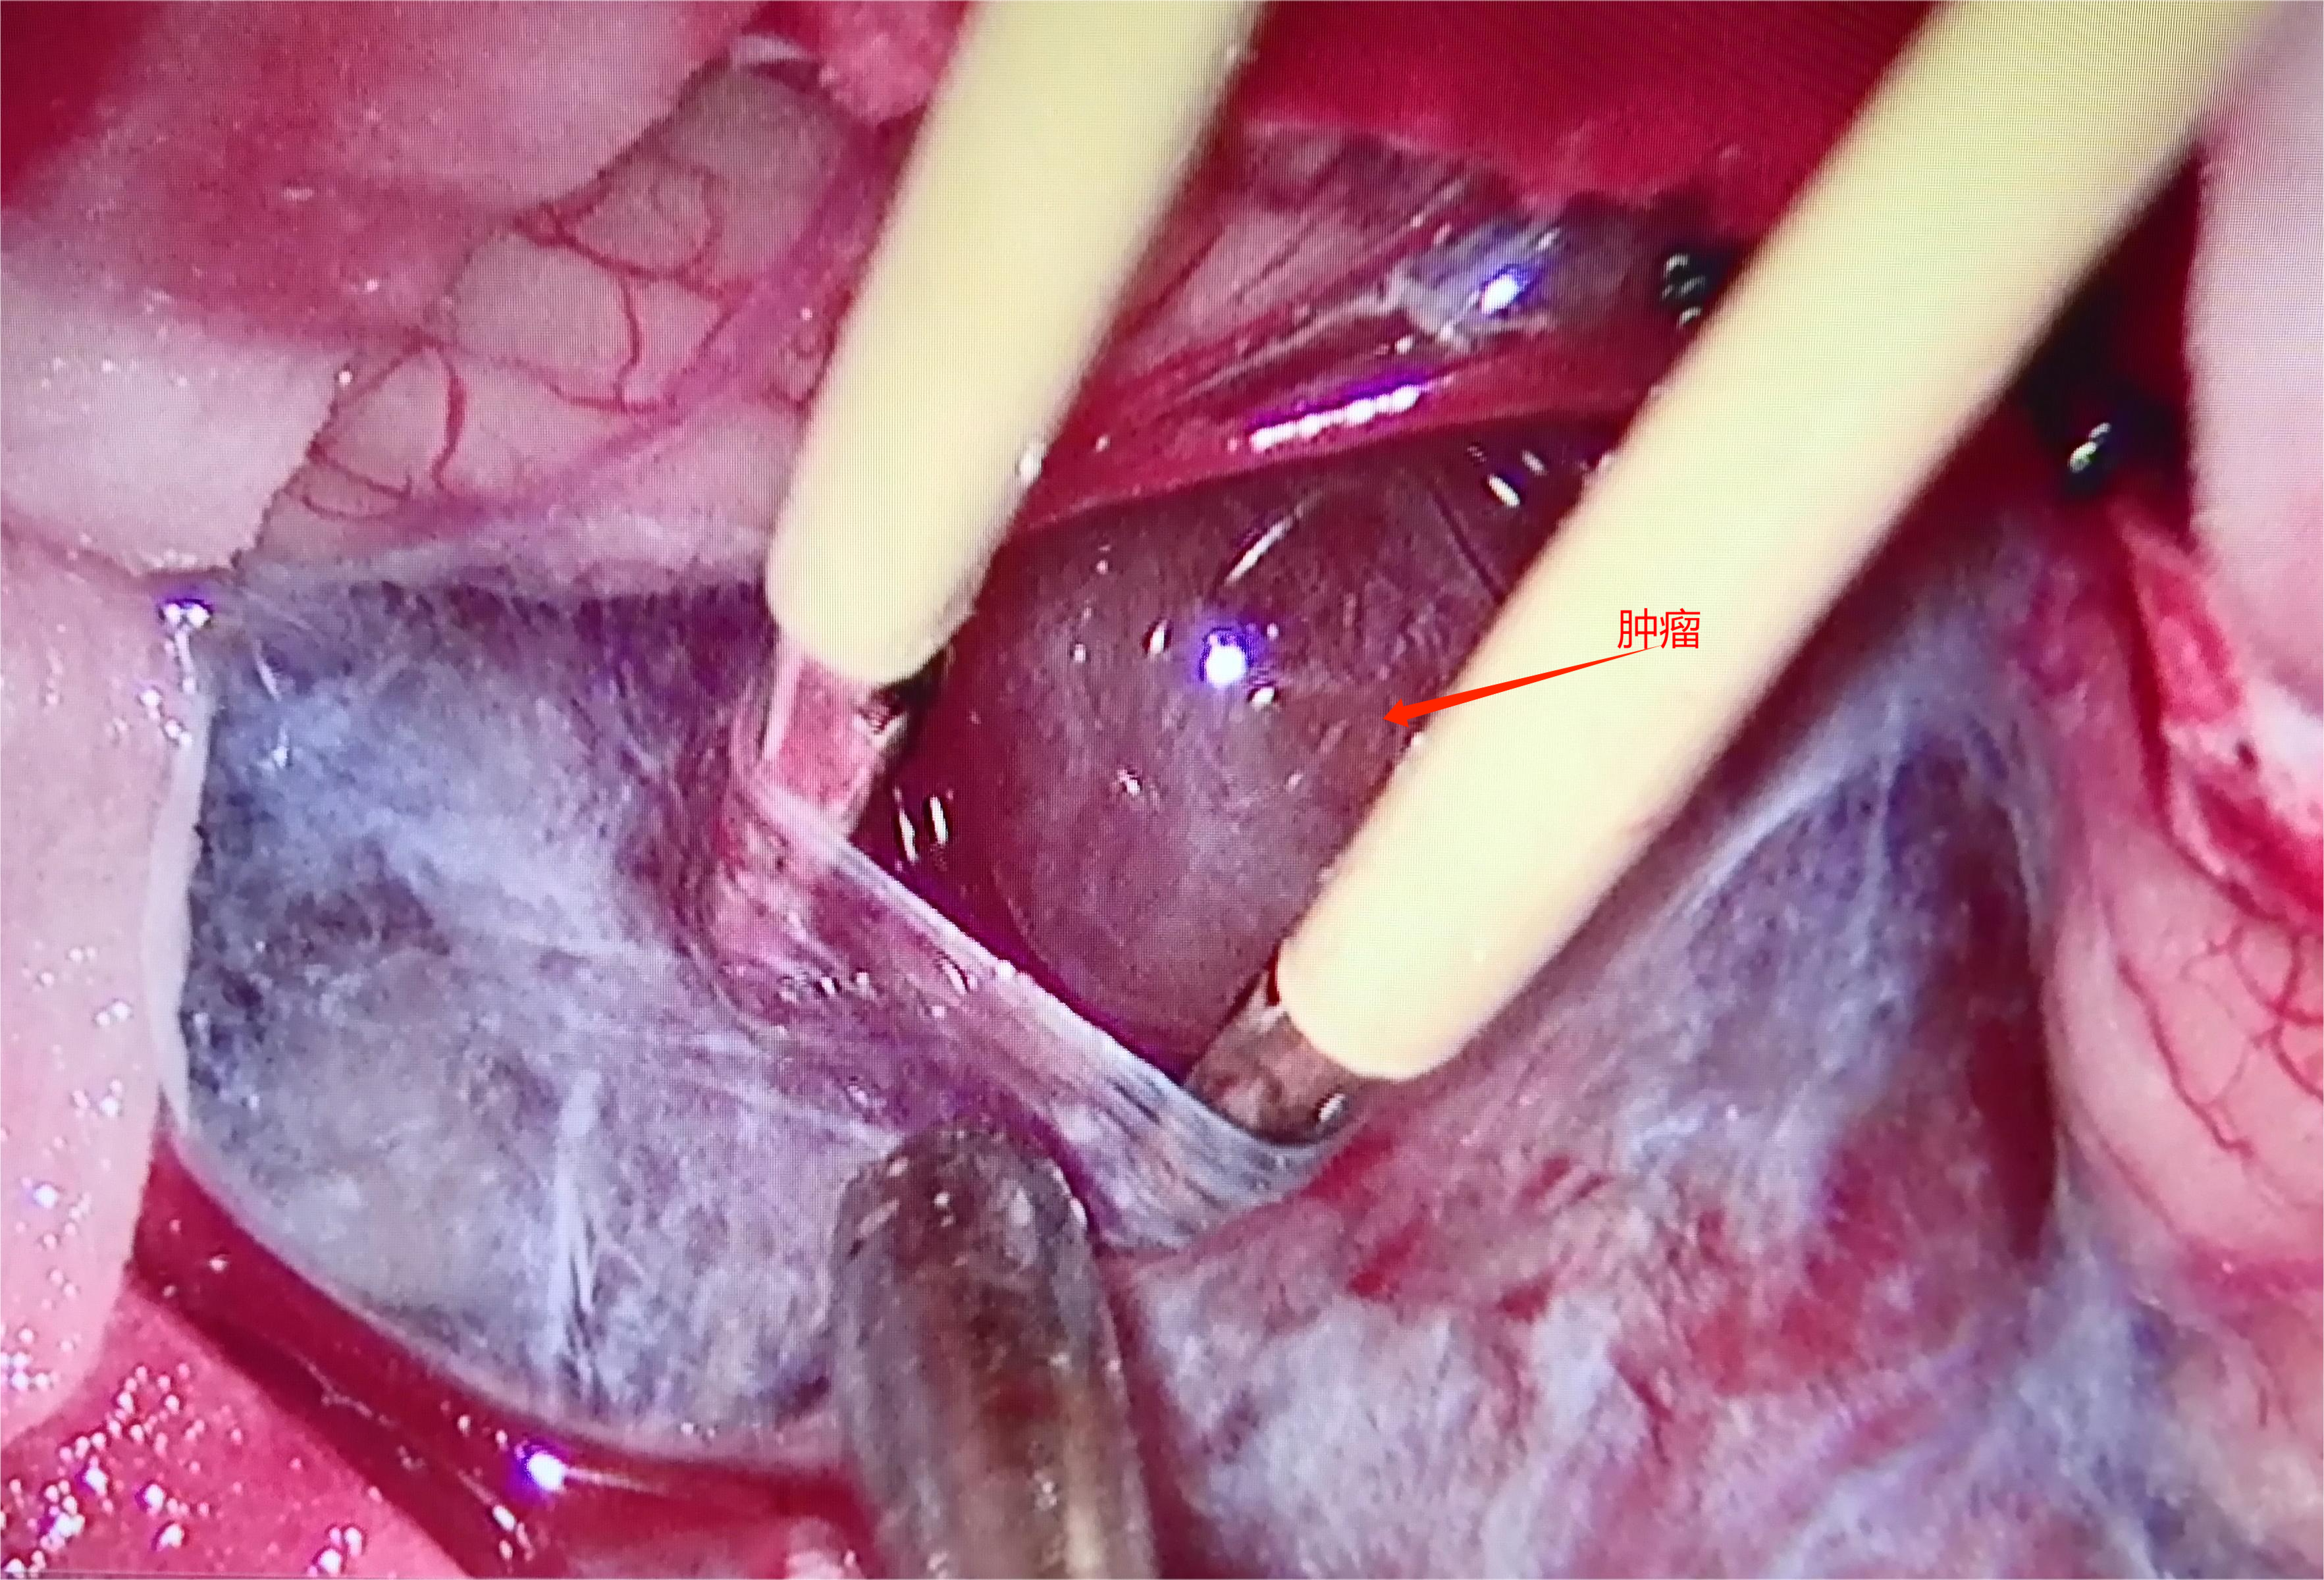

术中情况

充分暴露,分离边界,阻断血供,整体切除

术后患者一般情况良好,无新发神经功能障碍,共济运动失调较前好转。

血管母细胞瘤是一种良性血管肿瘤,来自中胚层起源的胚胎残余物。患病率女性占优势。后颅窝血管母细胞瘤最常见的症状是颅内高压伴随的症状,其次是小脑功能紊乱,临床检查常发现视乳头水肿、共济失调、眼球震颤三联征。椎动脉造影在后颅窝深部病变中特别有用,特别是第四脑室和脑干的血管母细胞瘤,造影可以提供病变血管状态,对于制定正确的手术方法很重要。理想的外科治疗是彻底切除病变,包括壁结节的囊性形态和完整的实体肿瘤。术中有大出血的可能性,但是成功的根治性切除仍然是非常重要,甚至在第四脑室和脑干的血管母细胞瘤治疗过程过程中,我们仍然应该追求全切肿瘤。